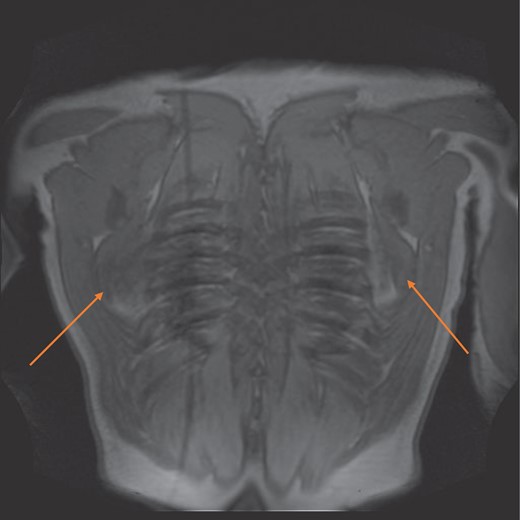

MRI confirmed the diagnosis and showed a second lesion on his left side, also at the infrascapular area (Figs 1–3). The patient had not complained of any symptoms to his left side or his left shoulder joint. After an extensive discussion with the patient and his family, we decided on a computerized tomography (CT) guided true cut biopsy to confirm the diagnosis (Fig. 4).

MRI coronal view of bilateral elastinfibromas (orange arrows).